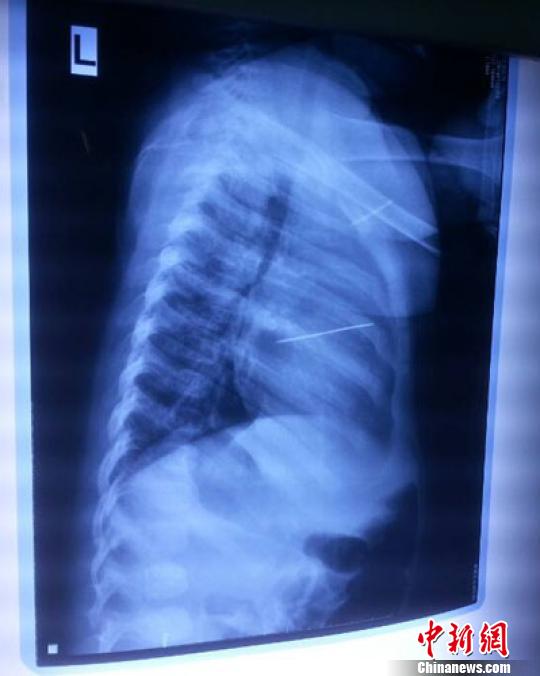

女嬰胸片提示心臟里面扎了一個縫衣針 蔡迅翔 攝

醫(yī)院胸心外科主任翟波介紹說,1月22日,小患者彤彤因為發(fā)燒抽搐來醫(yī)院就診,常規(guī)檢查時發(fā)現孩子心臟里面扎了一個縫衣針。

“第二天上午,我們做了個緊急彩超檢查,發(fā)現針是從患者右心室表面刺入,穿破室間隔,到達左心房,中間還有一部分損害到二尖瓣。于23號下午,我們就做了一個緊急手術,手術中發(fā)現,這枚針已經刺入心臟,沒入了右心室的下面,表面已經看不到針了,僅能看到一個小針眼,還在往外滲血,一點一點的滲,心包腔里面大概有100多毫升的出血,心包上一個洞,針在右心室表面刺入以后,穿過室間隔,在二尖瓣的上方,進入了左心房,在針的四周,有很多纖維沉積物,包繞著這枚針?!钡圆ㄕf,他們把針取出來以后,測量了一下,長度大概是五厘米,同時發(fā)現這個針給患者左心房的后壁造成了一定的損傷,左心房的后壁已經損傷了三分之二,還剩下有左心房的外膜,很薄的一層,如果這一層再破的話,這個孩子將會引起大出血,很快就會死亡。